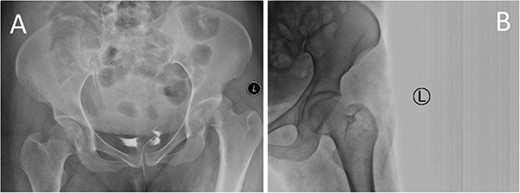

A medically free 42-year female presented to our institute as a life-saving case from a different hospital as she was a victim of unrestrained road traffic accident 2 days prior to presentation. Upon assessment in the emergency department (ER), she was conscious and oriented, and was found to have bilateral lung contusion, and multiple fractures of ribs. She also had a left sided vertical femoral head fracture dislocation comprising around 40% of the femoral head (Fig. 1). Closed reduction under conscious sedation was done in the ER, which was successful based on post-reduction imaging studies (Fig. 2). Her chest injuries were treated with chest tube and observation for 10 days. During that time, discussion was made with the patient regarding her situation and conservative management was chosen by way of bed rest and continuation of skeletal traction for 4 weeks with serial radiographs in the hospital on a weekly basis after clearance of her chest injuries. Skeletal traction was discontinued and she was advised to continue bed to wheelchair mobilization for an additional 2 weeks. After 6-weeks from the injury, a Computed Tomography (CT) was done to the patient and revealed signs of fracture healing (Fig. 3). At 3-years after the injury, she was found to have full painless range of motion of the affected hip and has resumed her activity of daily living without any complaints and the images showed a symmetrical joint space of the hips (Fig. 4).

Prereduction anteroposterior (AP) radiographs of the pelvis showing a left side fracture dislocation of the left proximal femur (A) and postreduction radiographs of the left hip (B) showing a concentric hip joint.